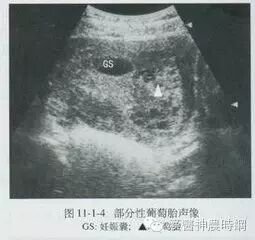

1.流产:葡萄胎病史与先兆流产相似,容易混淆,先兆流产有停经,阴道流血及腹痛等症状,妊娠实验阳性,但葡萄胎时多数子宫大于相应孕周的正常妊娠,HCG水平持续高值,B型超声图像不见胎囊及胎心搏动,而显示葡萄胎特点。

2双胎妊娠:子宫大于相应孕周的正常单胎妊娠,HCG水平也略高于正常,可与葡萄胎相混淆,但双胎妊娠无阴道流血,B型超声检查可以确诊。

3.羊水过多:一般发生于妊娠期,若发生于妊娠中期,因子宫迅速增大,需与葡萄胎相鉴别,羊水过多时无阴道流血,HCG水平在正常范围,B型超声检查可以确诊。